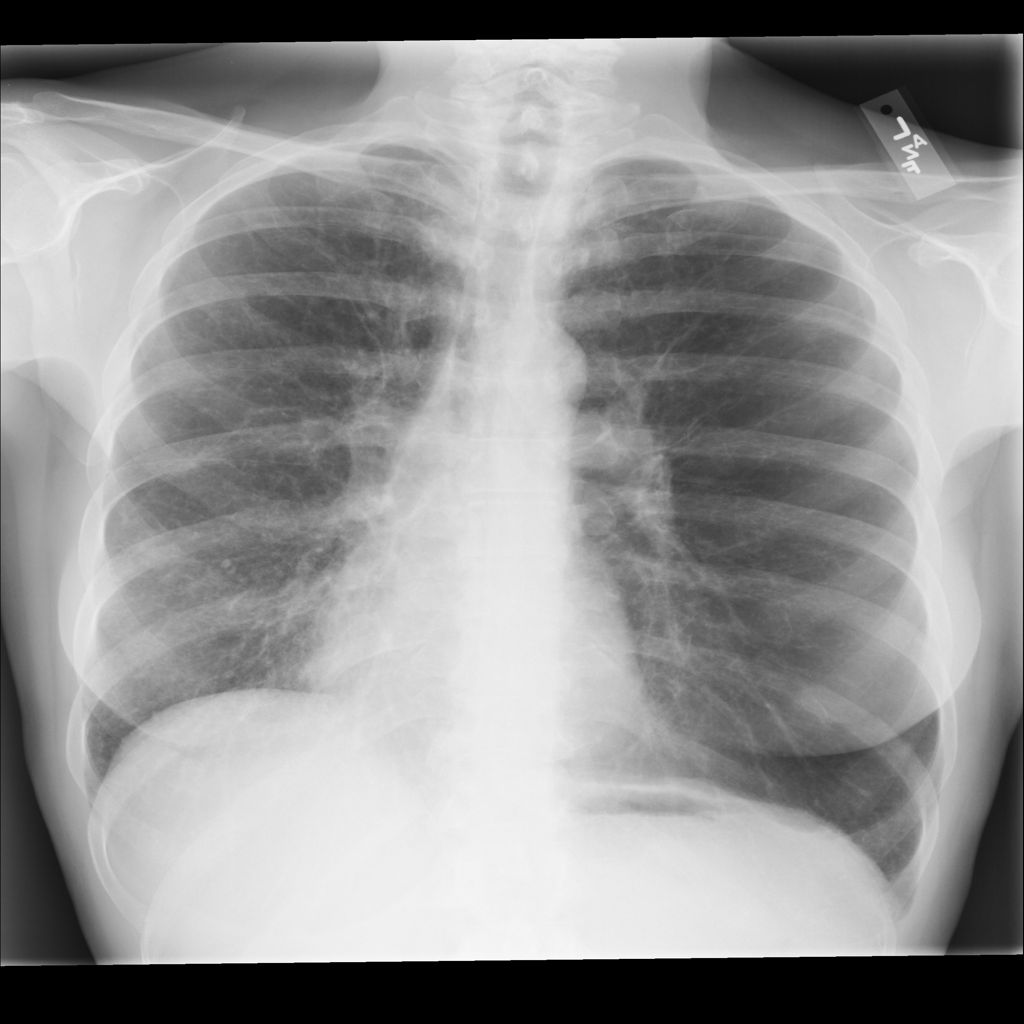

PAT-0E82 · IMG-000Emphysema

PAT-0E82 · IMG-000

AP